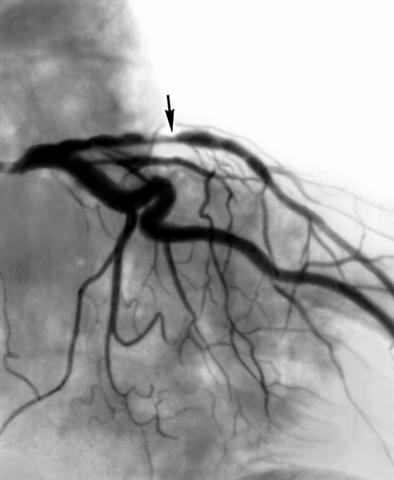

Рис. 1а). Коронарограммы при стенозе передней межжелудочковой ветви левой венечной артерии до рентгеноэндоваскулярной дилатации (стрелкой показано место стеноза).